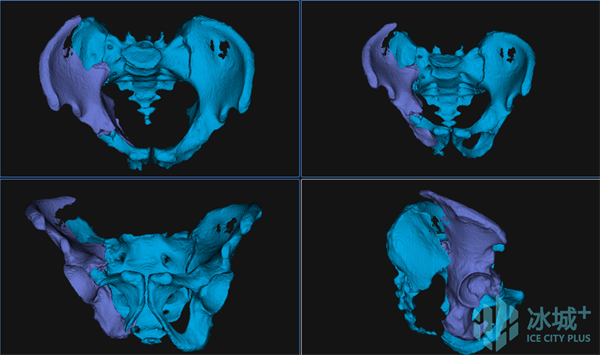

图1 患者术前影像资料

术前,刘建宇教授团队充分讨论,采用目前全球最先进的智能化骨科手术机器人全流程辅助骨盆骨折闭合复位内固定手术治疗。基于患者术前影像,借助基于AI与大数据的自动手术规划,将患者健侧肢体进行镜像配准,通过精细化自动分割与重建,实现个性化、定量化的复位规划。